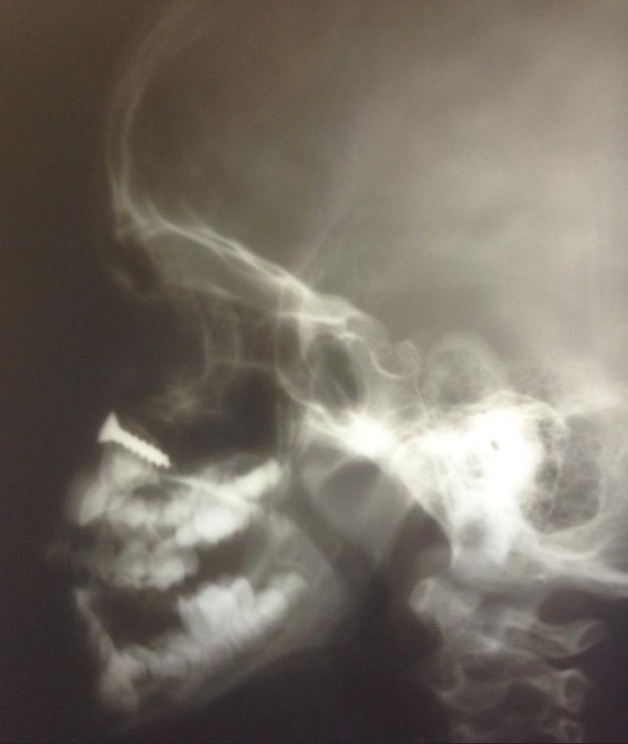

В Подмосковье врачи извлекли из носа пятилетней девочки шуруп, который находился там около года. Как сообщает пресс-служба министерства здравоохранения Московской области, инцидент произошёл в Клинской городской больнице. Предмет был случайно обнаружен при медицинском осмотре для дальнейшего оформления девочки в социально-реабилитационный центр для несовершеннолетних.

– Предмет находился в носу ребёнка около года, так как при изъятии был заржавевшим и полуразрушенным, – рассказала и.о. главного врача больницы Ольга Стебловская.